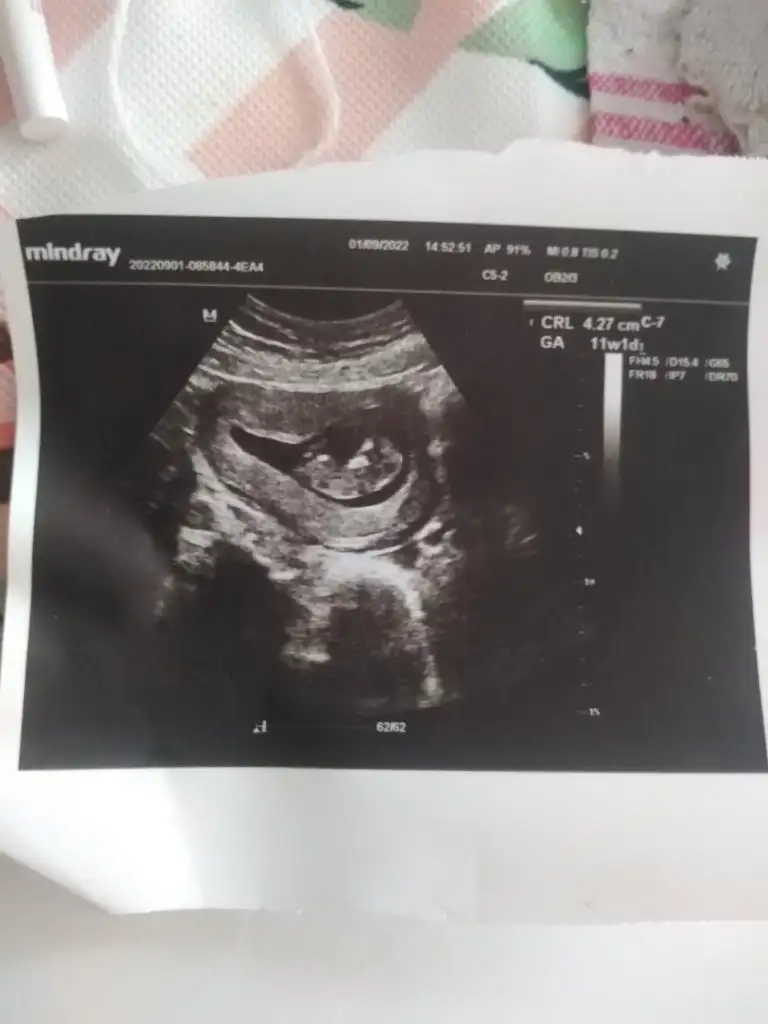

Lütfen lütfen bana da yorum yaparmisiniz biri 6 haftalik digeri 11 haftalik🙏🙏🙏